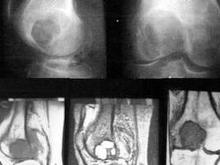

与骨恶性纤维组织细胞瘤[1]相对应,有骨良性纤维组织细胞瘤(benign fibrous histiocytoma of bone,BFH),BFH与非骨化性纤维瘤(nonossifying fibroma,NOF)及干骺端纤维性缺陷(metaphysial fibrous defect,MFD)三者在组织形态上相似,有时把其列为同一种疾病,使三病在名称上较为混乱。